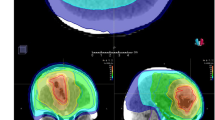

PFS, OS, and MFS were assessed at 3, 5, and 10 years. Of the 12 studies included in our meta-analysis, 11 studies (219 in the GTR + PORT cohort and 189 patients in the GTR cohort) reported relevant data regarding PFS following GTR for intracranial SFT. Serial HRs for the 3-, 5-, and 10-year PFS revealed that PORT after GTR demonstrated statistically significant superiority over GTR alone, sustained up to the 10-year follow-up (Fig. 2). The actuarial 3-, 5-, and 10-year PFS rates in the GTR + PORT cohort were 90.3%, 82.2%, and 53.3%, respectively, whereas those in the GTR cohort were 77.1%, 60.6%, and 31.8%, respectively (Fig. 3A and Table 2).

Kaplan–Meier curves for (A) progression-free survival (PFS), (B) overall survival (OS), and (C) metastasis-free survival (MFS) of the gross total resection (GTR) + postoperative radiotherapy (PORT) cohort and GTR cohort. The GTR + PORT cohort showed higher 3-, 5-, and 10-year PFS and OS, while MFS showed no significant difference between the groups.

OS in the GTR + PORT versus GTR groups

Overall, 362 patients (196 in the GTR + PORT vs. 166 in the GTR cohort) from nine studies were analyzed to compare OS between the cohorts. Similarly, pooled analysis of studies showed a significant advantage of PORT over GTR alone in all OS periods (Fig. 4). The actuarial 3-, 5-, and 10-year OS rates in the GTR + PORT cohort were 98.3%, 96.6%, and 81.4%, respectively, whereas those in the GTR cohort were 93.2%, 88.5%, and 70.3%, respectively (Fig. 3B and Table 2).

MFS in the GTR + PORT versus GTR groups

Four studies comprising 105 patients who underwent PORT and 90 who underwent surgery only were included in the analysis of MFS. However, pooled HR showed no significant advantage of PORT after GTR over GTR alone for intracranial SFT (Fig. 5), although moderate heterogeneity was observed in the 10-year MFS analysis (I2 = 34%). The actuarial 3-, 5-, and 10-year MFS rates were 96.6%, 92.8%, and 65.2% in the GTR + PORT cohort and 91.8%, 88.9%, and 81.3% in the GTR cohort, respectively (Fig. 3C and Table 2).